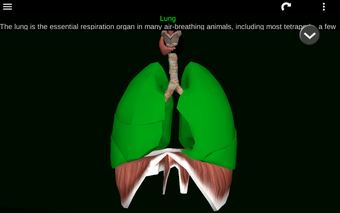

Diese Anwendung zeigt ein dreidimensionales Modell der menschlichen Körperorgane und eine Beschreibung aller von ihnen.

Sie können jedes Organ wie Herz, Gehirn, Lunge, Fortpflanzungssystem, Leber, Darm, Eierstock, Hoden, Magen, Niere usw. anfassen.

Sie ist für alle Menschen nützlich, auch für Studenten, da jedes Anatomieorgan in einer anderen Farbe dargestellt ist.

Sie können die App verwenden, um herauszufinden, welches die verschiedenen Körperorgane sind und welche Funktionen sie haben.